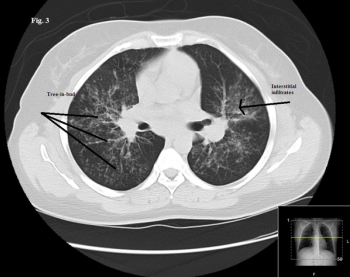

Worsening respiratory symptoms and fatigue of 6 months’ duration brought a 44-year-old woman in for evaluation. Diagnosed with asthma 2 years earlier, she was compliant with, but unresponsive to treatment. Your impressions?